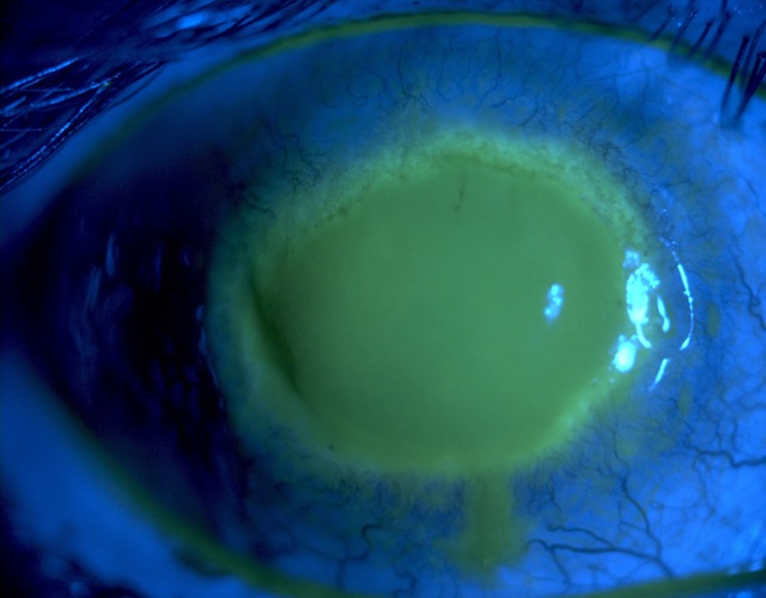

- 고리형 각막침윤(ring infiltrate): 면역 반응에 의한 고리 모양 침윤

- 진행기: Ring infiltrate — 가장 특징적 후기 소견

- 고리형 침윤(ring infiltrate) = AK의 가장 특징적 후기 소견